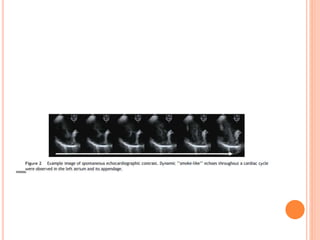

SPONTANEOUS ECHO CONTRAST

 The incidence of spontaneous echo contrast in

mitral stenosis varies from 21 to 67%.

 Previous reports have shown that in majority or all,

left atrial clot and systemic thromboembolization

were associated with spontaneous echo contrast in

left atrium on transesophageal echocardiography.

 Spontaneous echo contrast was also found to be

an important predictor of systemic embolization,

independent of the presence of clot in LA clot.

SPONTANEOUS ECHO CONTRAST The incidence of spontaneous echo contrast in mitral stenosis varies from 21 to 67%.  Previous reports have shown that in majority or all, left atrial clot and systemic thromboembolization were associated with spontaneous echo contrast in left atrium on transesophageal echocardiography.  Spontaneous echo contrast was also found to be an important predictor of systemic embolization, independent of the presence of clot in LA clot.